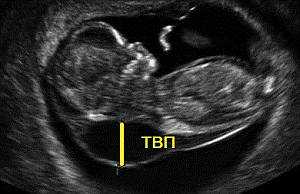

- Толщина воротникового пространства (как косвенный маркер синдрома Дауна, оценивается в сроке до 13 недель).